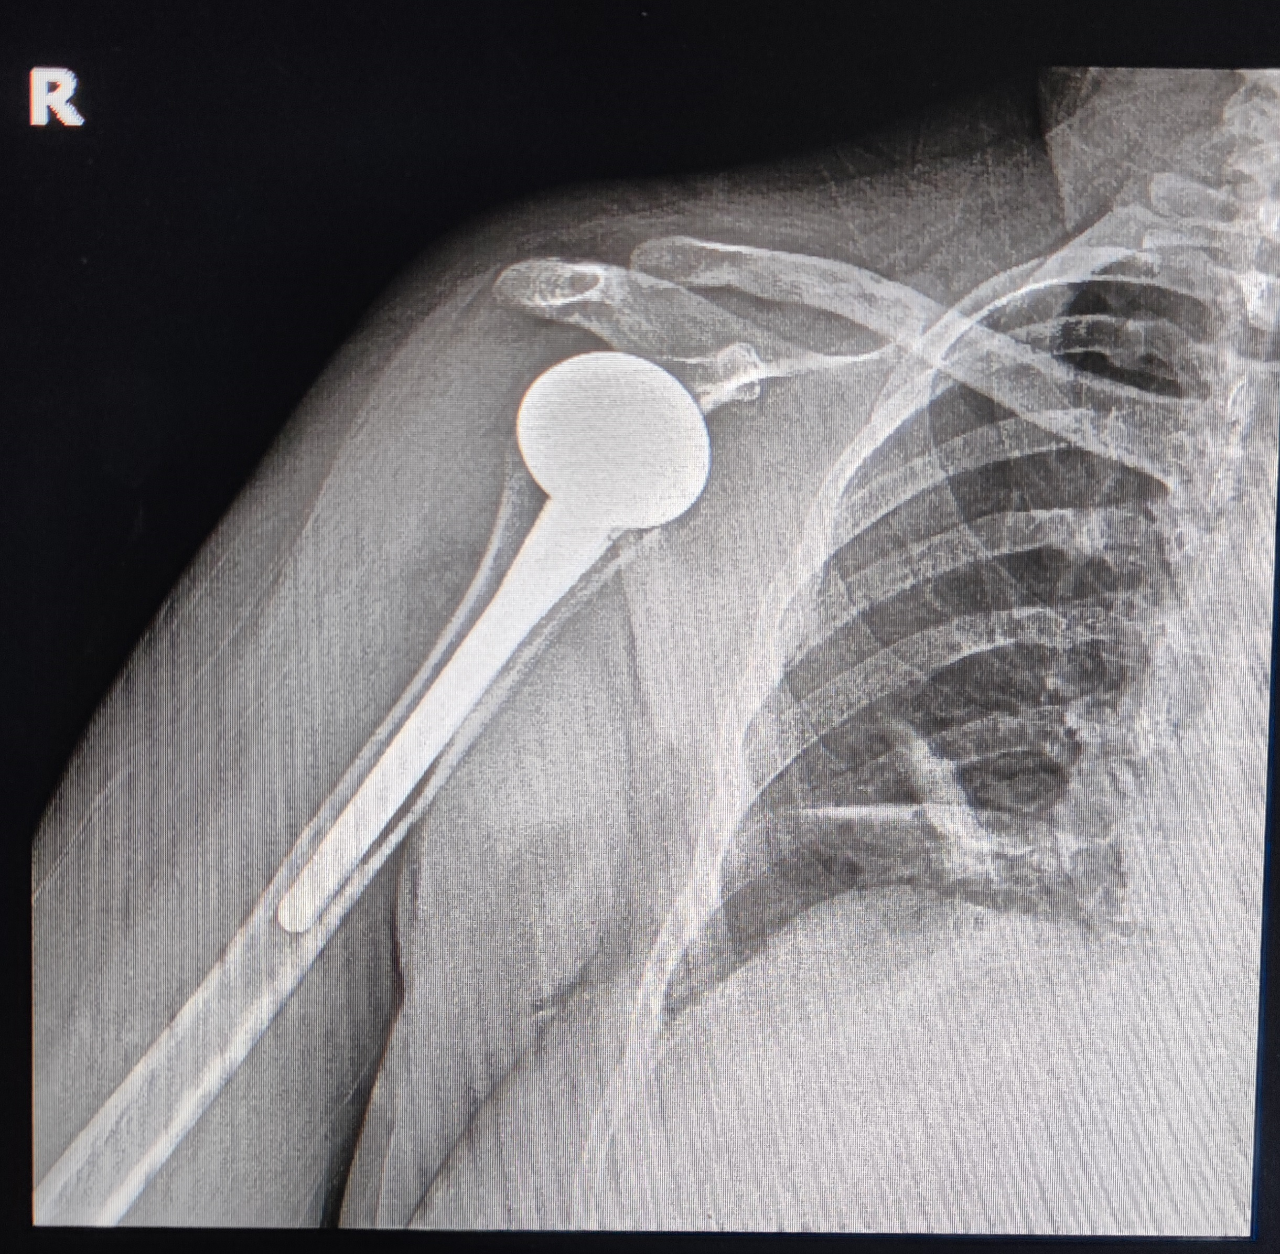

六、解剖型全肩关节置换术(Anatomical total shoulder replacement, ATSR)与全反式全肩关节置换术(Reverse total shoulder replacement, RTSR)。ATSR与RTSR是解决肩关节退变与骨折的重要方法,但其手术技术具有一定的难度、有一定的学习曲线。在以色列,我更为系统地学习了ATSR与RTSR手术技术,对肩关节置换有了更深入的掌握与理解。